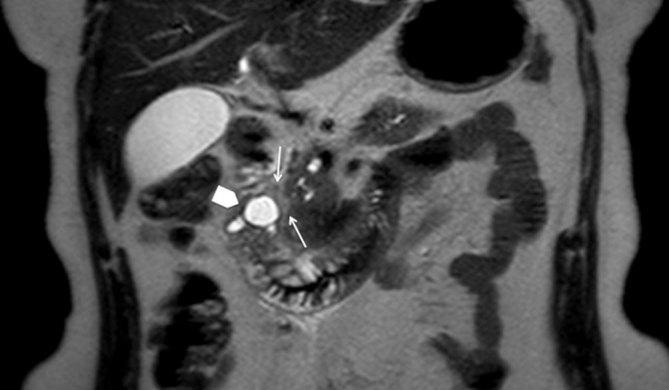

Cystic dystrophy of the duodenal wall in heterotopic pancreas, recently described as paraduodenal pancreatitis, is a rare condition characterized by multiple cysts or pseudocysts located in the submucosa or muscularis propria of a thickened duodenal wall. They result from multiple episodes of obstruction of the small ducts in aberrant pancreatic islets. Cystic dystrophy of the duodenal wall in heterotopic pancreas usually affects alcoholic males, but here we present the case of a female without a history of alcohol abuse who was referred to our emergency department with abdominal pain and vomiting. She was treated by a pancreas-preserving surgical approach, thanks to a proper pre-operative differential diagnosis. Even though differentiating this benign condition from pancreatic cancer is a challenge, some characteristic findings on multidetector CT scan and MRI/MR cholangiopancreatography, such as a thickened duodenal wall containing cysts and sheet-like tissues in the pancreaticoduodenal groove, could lead to the correct diagnosis.

十二指肠壁囊肿性营养不良合并异位胰腺,最近被描述为十二指肠旁胰腺炎,是一种罕见的病症,其特征是在增厚的十二指肠壁的黏膜下层或固有肌层中存在多个囊肿或假性囊肿。它们是由异常胰岛中小导管的多次梗阻引起的。十二指肠壁囊肿性营养不良合并异位胰腺通常影响男性酗酒者,但在此我们报告一例无酗酒史的女性病例,该女性因腹痛和呕吐被转诊至我们的急诊科。由于术前进行了恰当的鉴别诊断,她接受了保留胰腺的手术治疗。尽管将这种良性病症与胰腺癌区分开来具有挑战性,但多排CT扫描和MRI/MR胰胆管造影的一些特征性表现,如十二指肠壁增厚并伴有囊肿以及胰十二指肠沟内的片状组织,可有助于做出正确诊断。